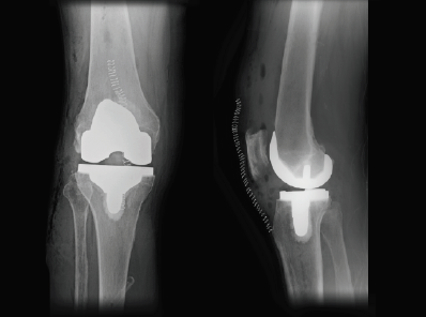

Robotic knee surgery is a game-changer for individuals suffering from arthritis, chronic pain, or joint damage. Using the MAKO robot, Dr. Cahill ensures each step of the surgery is performed with unparalleled accuracy, helping you get back to what matters faster and with less discomfort.

If you’re experiencing knee pain that hasn’t responded to conservative treatments, a robotic-assisted knee replacement may be the answer. With personalized surgical plans and less invasive techniques, you can expect better joint function and a shorter recovery time.

For patients seeking hip replacement in Houston, MAKO robotic-arm technology supports a customized approach to implant placement. By mapping your joint’s anatomy in advance, Dr. Cahill achieves a level of surgical precision that minimizes complications and enhances implant longevity.